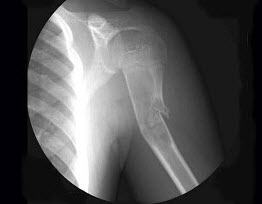

3、多项选择题 肱骨外科颈骨折,正确的摄片体位是()

A.肱骨上端正位

B.肱骨上端侧位

C.肱骨上端正侧位

D.肱骨上端斜位

E.肱骨上端穿胸位